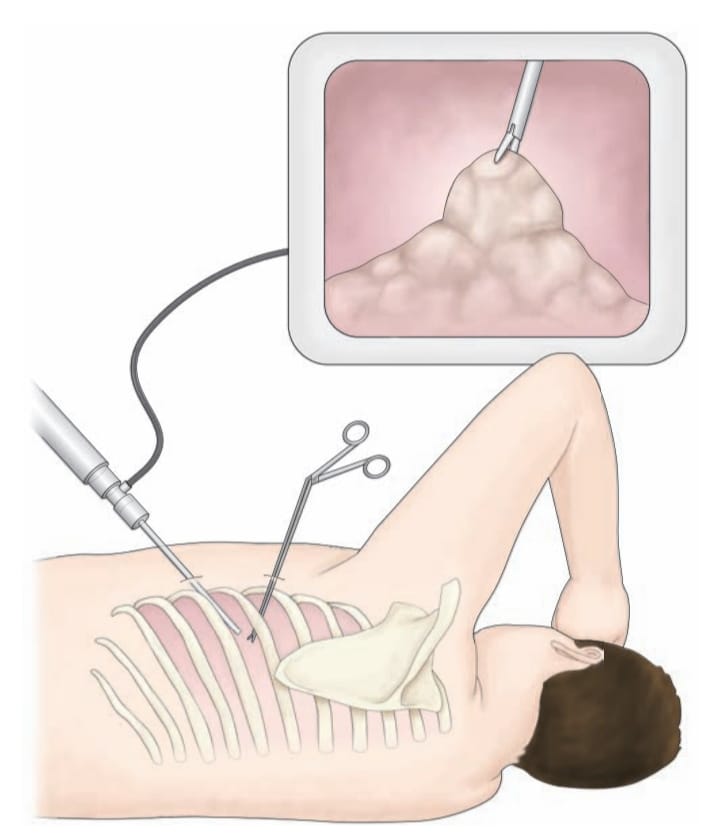

Thoracoscopy (થોરાકોસ્કોપી):

- થોરાકોસ્કોપી એ એક ડાયગ્નોસ્ટિક પ્રોસિઝર છે જેમાં એન્ડોસ્કોપની મદદથી પ્લુરલ કેવીટીને એક્ઝામીન કરવામાં આવે છે.

- આ પ્રોસિજરમાં ચેસ્ટ વોલમાં નાનામાં નાનું ઇનસિઝન મુકવામાં આવે છે અને આ ઇનસિઝન મારફતે એન્ડોસ્કોપને પ્લુરલ કેવીટીમાં ઇન્સર્ટ કરવામાં આવે છે અને તે એરિયાનું ડાયરેક્ટ એક્ઝામિનેશન કરવામાં આવે છે.

- આ સ્પેશિયલાઇઝ એન્ડોસ્કોપમાં નેરોઇંગ ટ્યુબ આવેલ હોય છે અને તેમાં આવેલ કેમેરા અને લાઇટ દ્વારા થોરાસિક એરિયાને વિઝયુલાઇઝ કરવામાં આવે છે.

- થોરાકોસ્કોપીની મદદથી પ્લુરલ ઇફ્યુઝન, પ્લુરલ ડીઝીસ અને Tumor ના સ્ટેજિંગ ને ડાયગ્નોસ કરી શકાય છે આ ઉપરાંત થોરાકોસ્કોપીની મદદથી બાયોપ્સી પણ કલેક્ટ કરવામાં આવે છે.